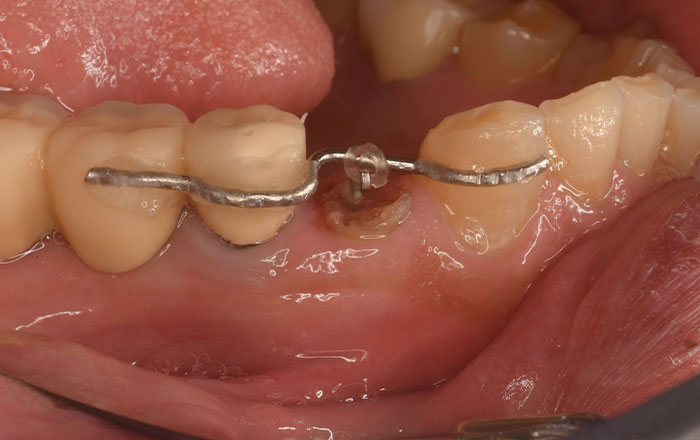

スケーリング(保険適用)

スイス・EMS社製の超音波スケーラーで、歯の表面や歯と歯茎の間にある歯垢や歯石を痛みなく取り除きます。